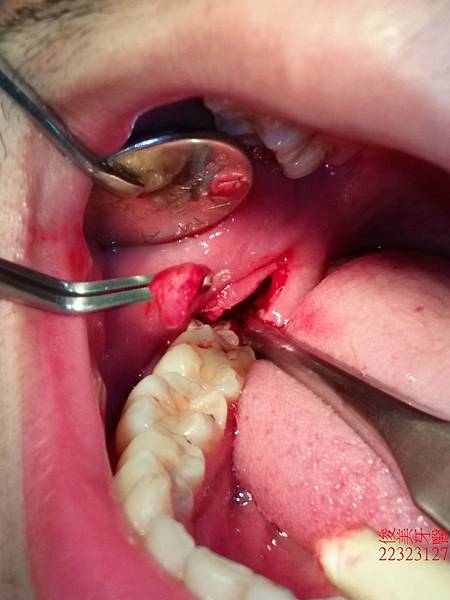

打開後取出一些發炎組織。

牙齒大且牙根因彎曲抓地力強,需要經驗熟且豐富的醫師來處理。

雖然費了一點時間,但我們還是順利將其全部取出。